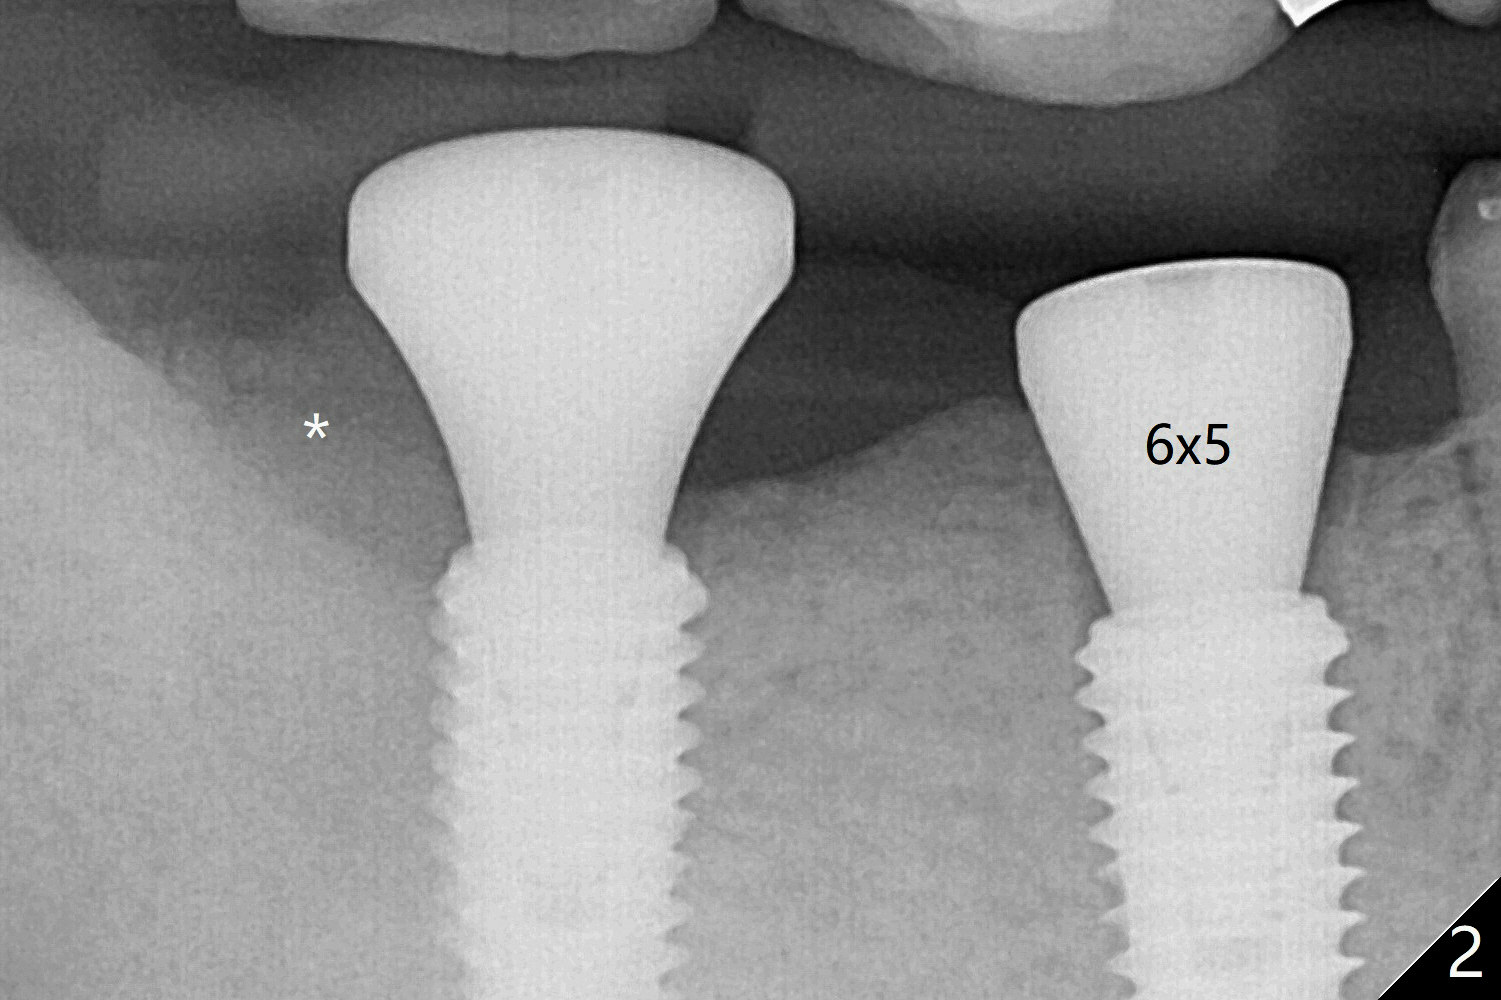

The bone at #30 and 31 is so hard that plenty of bone shaving is saved as bone graft to be placed in the socket of #31 (Fig.2 *). More graft is placed after placement of a healing abutment. No provisional is fabricated because of limited vertical space. The patient is hesitant about apicoectomy. After discussion of advantages and disadvantages of the latter vs. extraction and implant, the patient chooses the extraction. The latter turns out to be smooth with socket preservation (Fig.5, 6 *). Immediately postop PA shows bone loss at #30 and minor degree around the apex of #31 implant (Fig.4 <), which is related with hard bone and bone necrosis due to heat. The bone loss around the implants at #30 and 31 persists 3.5 month postop, while the socket heals at #29 two months post socket preservation (Fig.9). When the healing abutments with heavy plaque (similar to that in Fig.7) are removed, there is granulation tissue around the gingival cuffs with tenderness. The abutments are reloaded after cleaning with OHI. Gingiva becomes inflamed at #31 when a splinted provisional is being worn to intrude the opposing supraerupted teeth; bone resorption remains severe in the previous distal socket and the mesial necrotic area (Fig.13 S, N). Oral hygiene is bad.